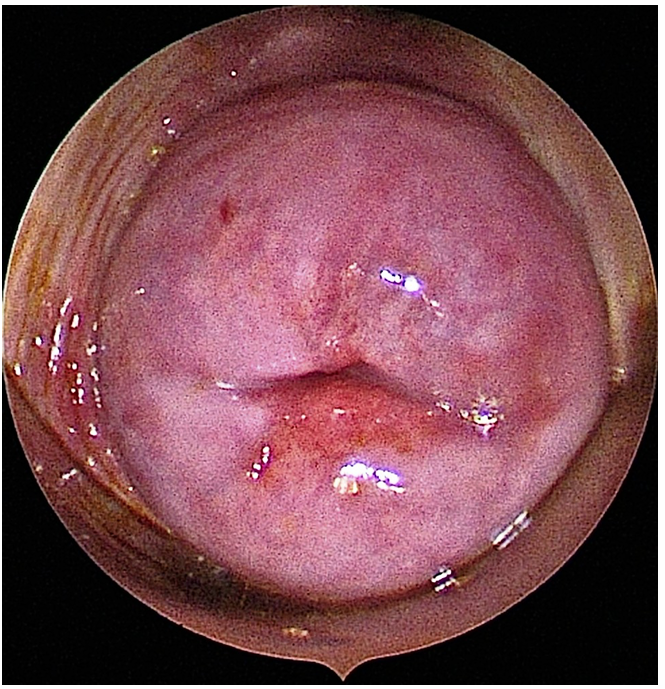

A hysteroscopy is a procedure that allows your doctor to look inside your uterus (womb) to diagnose and treat causes of abnormal bleeding or fertility issues. We use a hysteroscope-a thin, lighted telescope-like instrument. It is inserted through the vagina and cervix into the uterus. Because it enters through natural pathways, there are no cuts or incisions on your skin.

1. Diagnostic Hysteroscopy: Used to simply “look” and diagnose problems like polyps, fibroids, or structural issues.

2. Operative Hysteroscopy: If a problem is found during the diagnosis, we can often use specialized, slender instruments to correct the issue mmediately (e.g., removing a polyp).

4. We release a fluid (usually saline) to expand the uterus, giving us a clear view of the lining and the openings of the fallopian tubes.